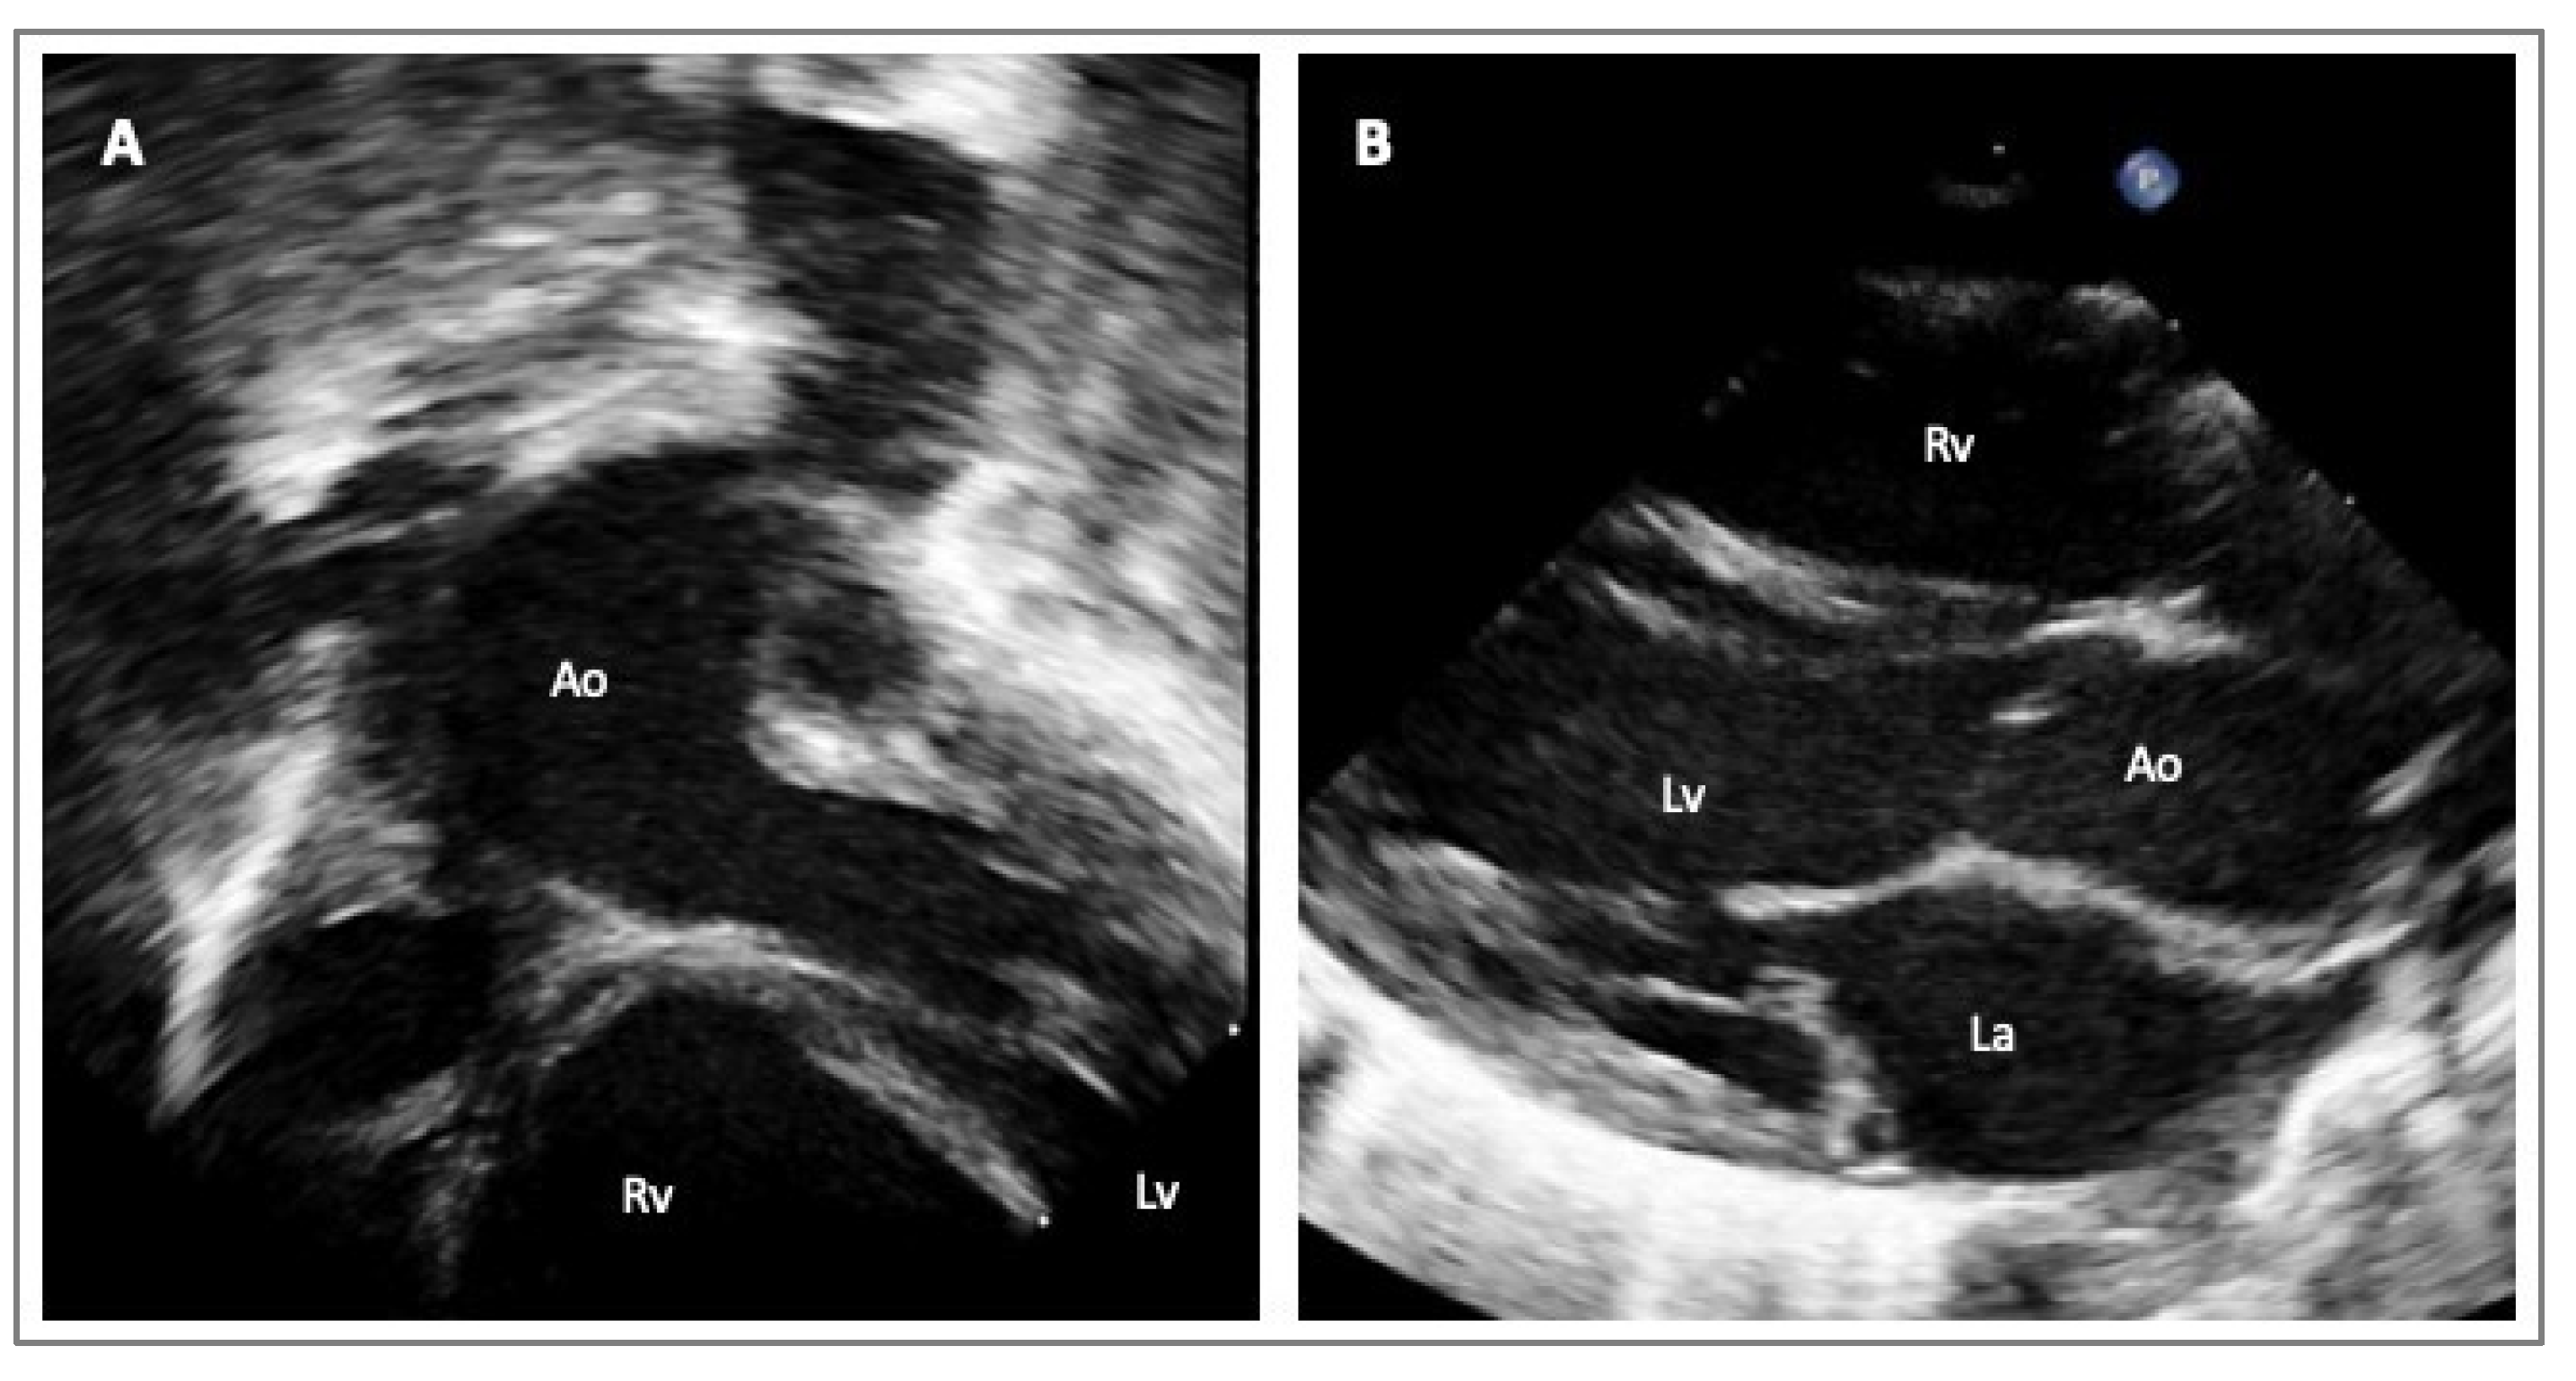

4. Imaging in HTADs

- Evangelista, A.; Sitges, M.; Jondeau, G.; Nijveldt, R.; Pepi, M.; Cuellar, H.; Pontone, G.; Bossone, E.; Groenink, M.; Dweck, M.R.; et al. Multimodality imaging in thoracic aortic diseases: A clinical consensus statement from the European Association of Cardiovascular Imaging and the European Society of Cardiology working group on aorta and peripheral vascular diseases. Eur. Heart J. Cardiovasc. Imaging 2023, 24, e65–e85. [Google Scholar] [CrossRef] [PubMed]